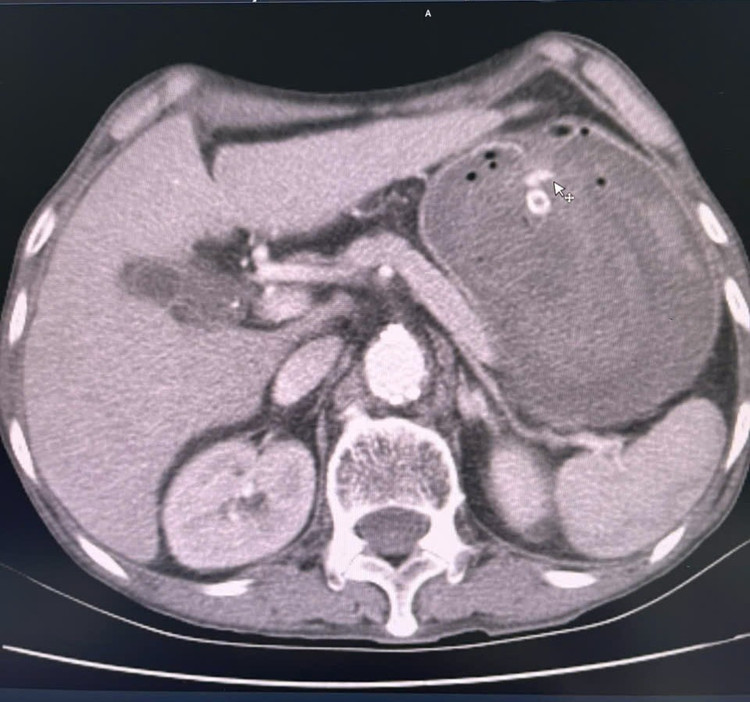

Chảy máu trên phim chụp cắt lớp - Ảnh BVCC

Qua chụp CT tiêm thuốc cản quang và chụp mạch trên máy DSA, thấy được vị trí chảy máu dạ dày tương đối lớn. Các bác sĩ đã tiến hành nút tắc toàn bộ nhánh động mạch chảy máu. Sau can thiệp, chụp kiểm tra lại, hệ thống động mạch không còn điểm chảy máu nào khác trong ống tiêu hóa.